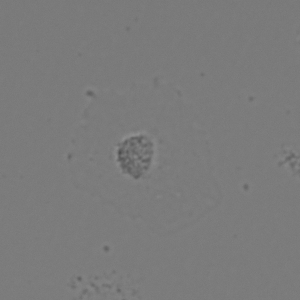

Figure 3: Original images of sequence is example of high dynamics of cell behavior affecting on contrast properties

The Fig.3 is representing couple of frames of sample image sequence with relatively high contrast between foreground and can be segmented with almost 95% accuracy with any method we used. Frame 1 of sample sequence presented at Fig.3(a) contain regions of hyper contrast pixels. In this case such condition does not affect on valid recognition since they are belong to object and present on margins of it and differs well from background. For Frame 2 there is absence of such pixels (Fig.3(b)) and this conditions also makes segmentation possible in relatively inflexible filtering conditions. The Frame 2 has relatively low contrast however it is seen that after filtration applied on image we achieve good difference of core and cell body compared to background as it presented at Fig.4 .